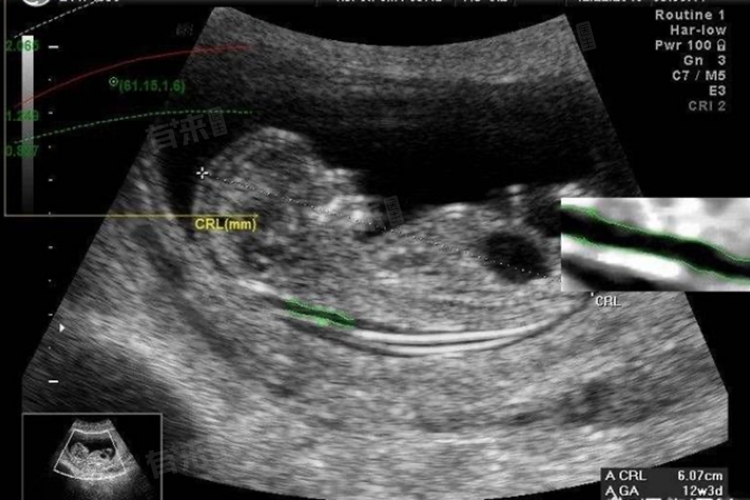

- NT检查,即颈项透明层厚度检查,是孕期早期的一项重要筛查手段,通常在孕11-13周+6天进行。通过测量胎儿颈部透明层的厚度,可以评估胎儿是否存在唐氏综合征等染色体异常的风险,这一检查对于早期发现胎儿问题、及时采取干预措施具有重要意义。